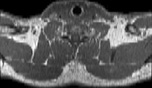

Visible Human male: Sectio transversalis 1279

CT

NMR

Pd T1 T2